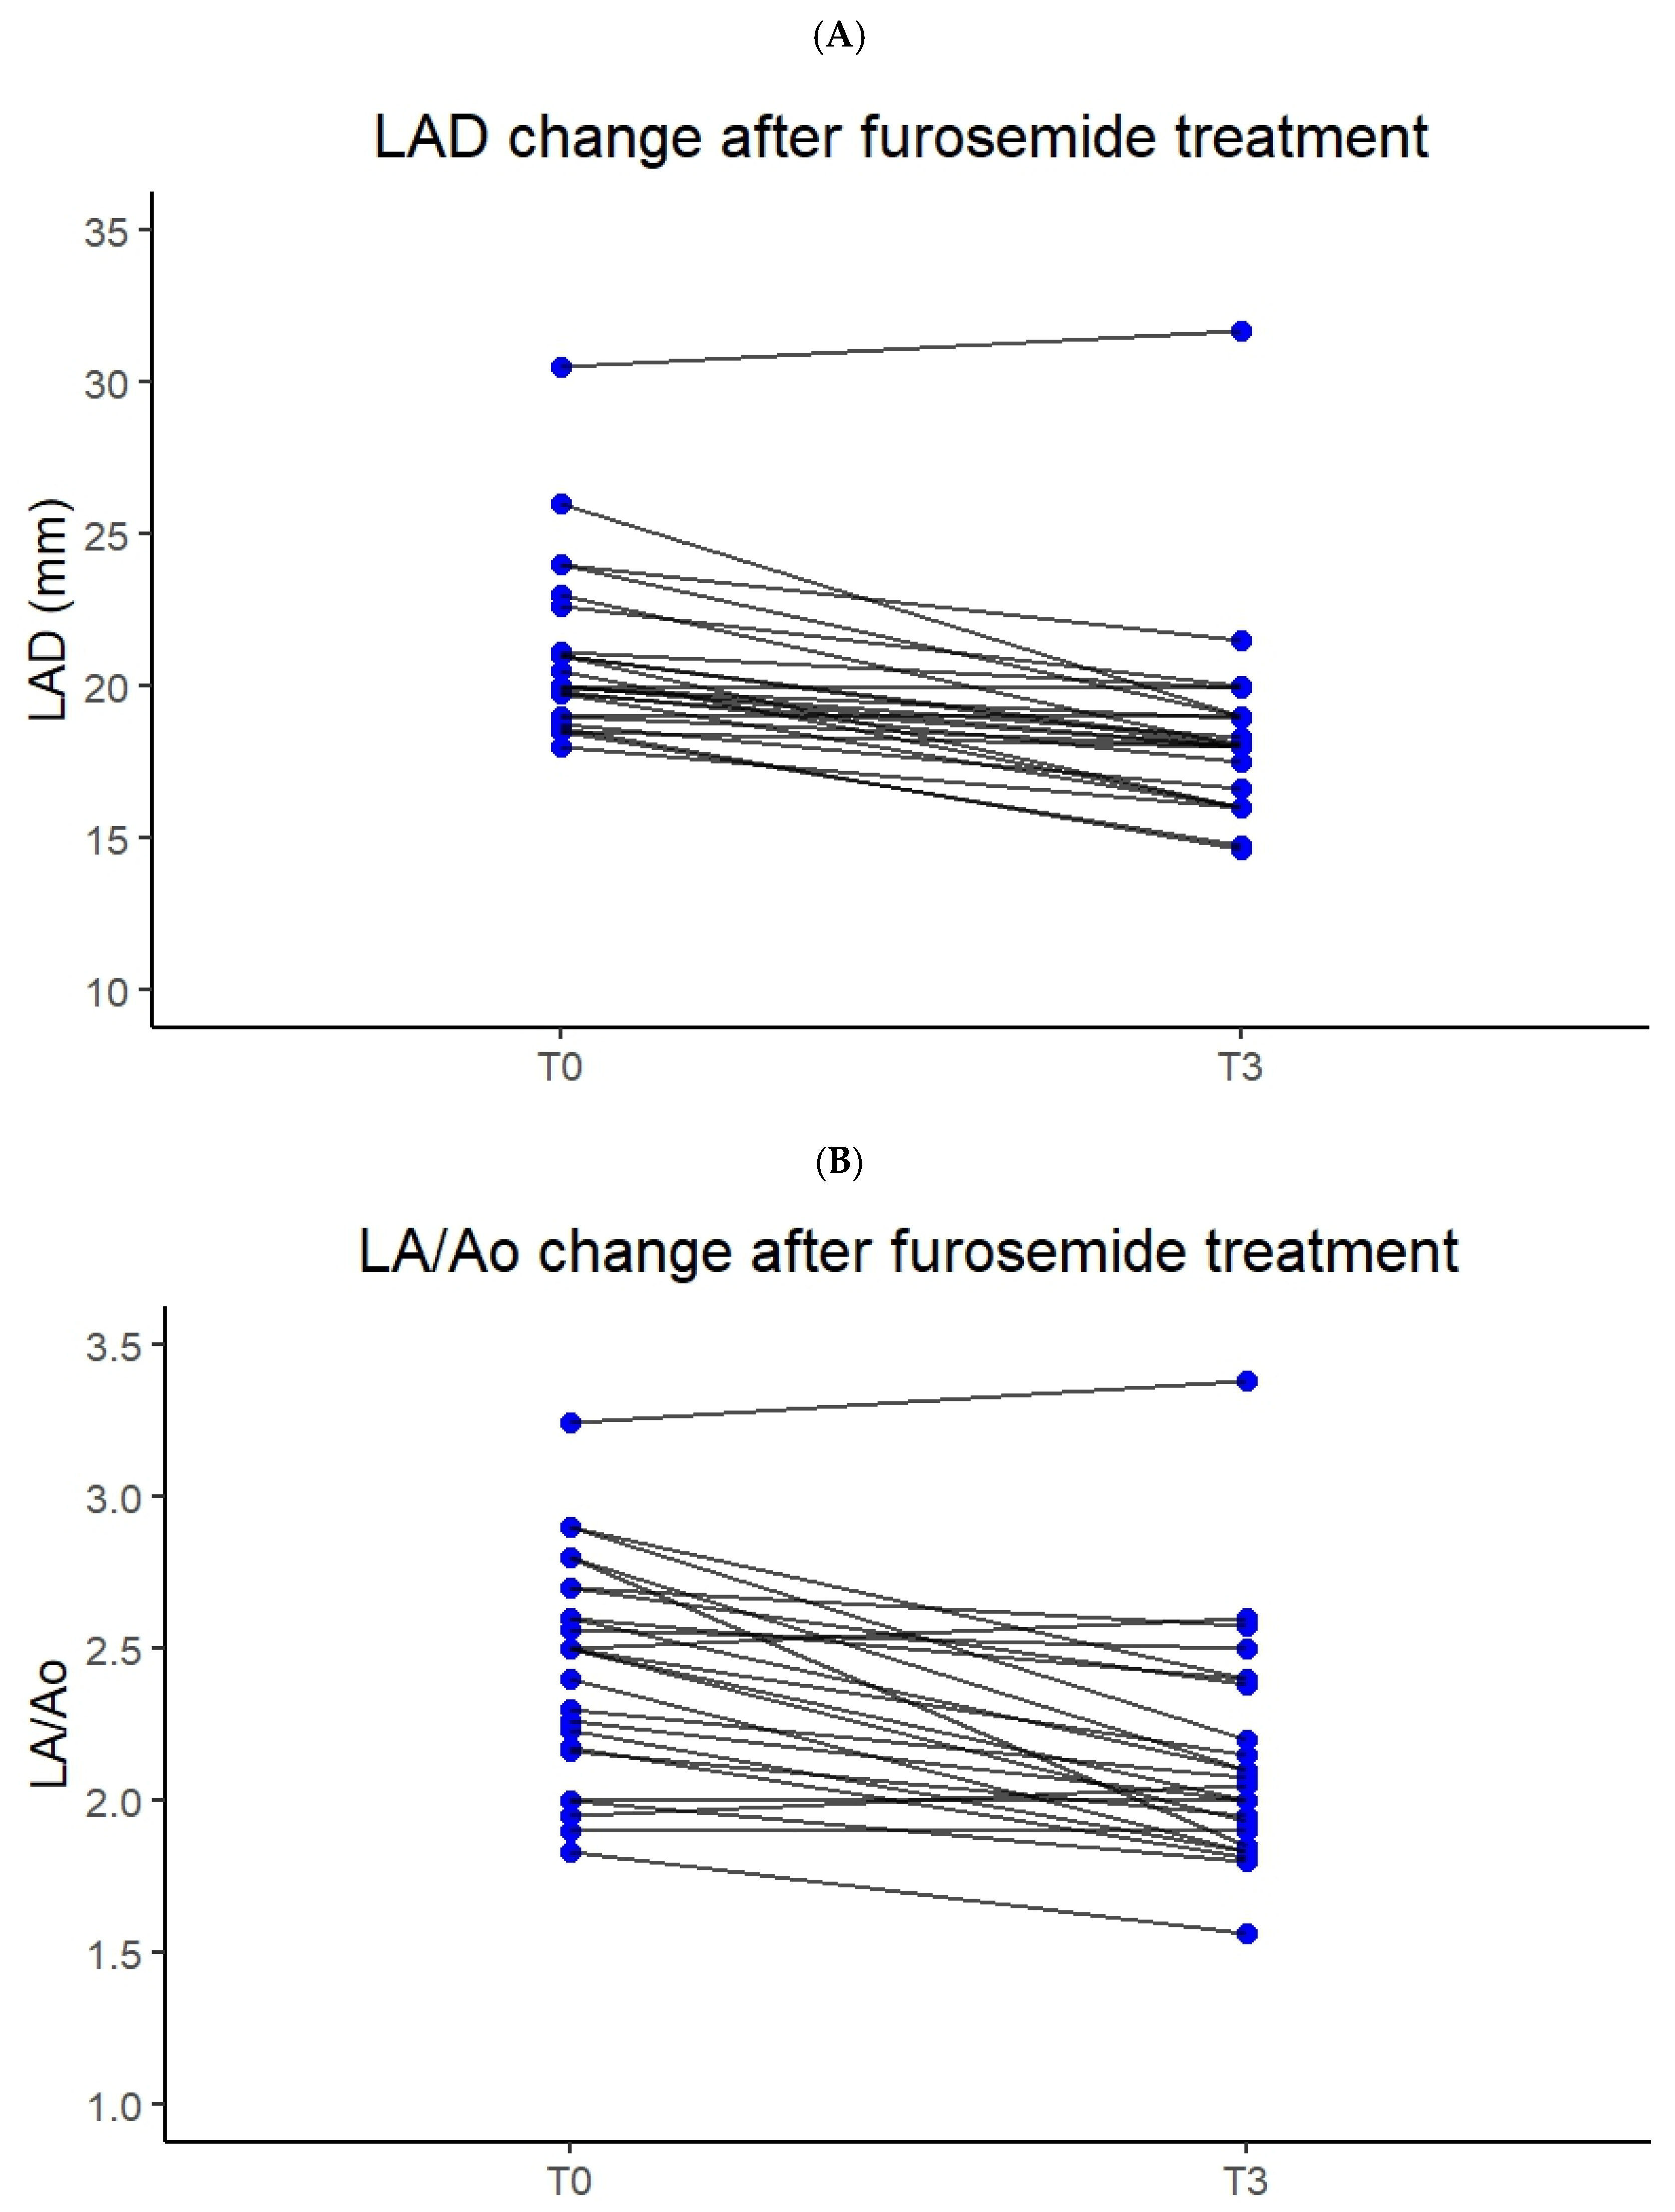

3.2. Correlation Between Furosemide Dose, Breathing Improvement and Left Atrial Size